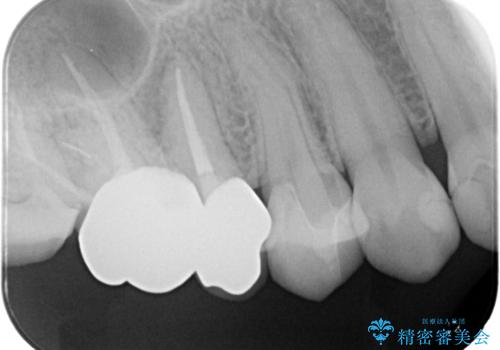

右上4番に歯冠色インレーが入っており、遠心側室エリアのマージン不適を認め、そこに汚れが溜まりやすい状態となっていました。

現在入っているインレー・CR裏層を除去し、再度CR裏層・セラミックインレー形成しました。